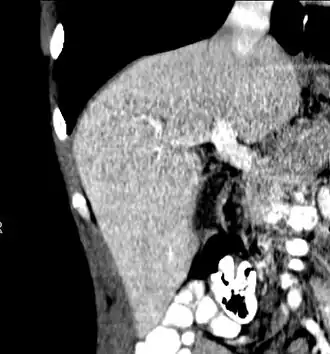

With the recent advances of noninvasive imaging, living liver donors usually have to undergo imaging examinations for liver anatomy to decide if the anatomy is feasible for donation. The evaluation is usually performed by multidetector row computed tomography (MDCT) and magnetic resonance imaging (MRI). MDCT is good in vascular anatomy and volumetry. MRI is used for biliary tree anatomy. Donors with very unusual vascular anatomy, which makes them unsuitable for donation, could be screened out to avoid unnecessary operations.

MDCT image. Arterial anatomy contraindicated for liver donation -

MDCT image. 3D image created by MDCT can clearly visualize the liver, measure the liver volume, and plan the dissection plane to facilitate the liver transplantation procedure. -